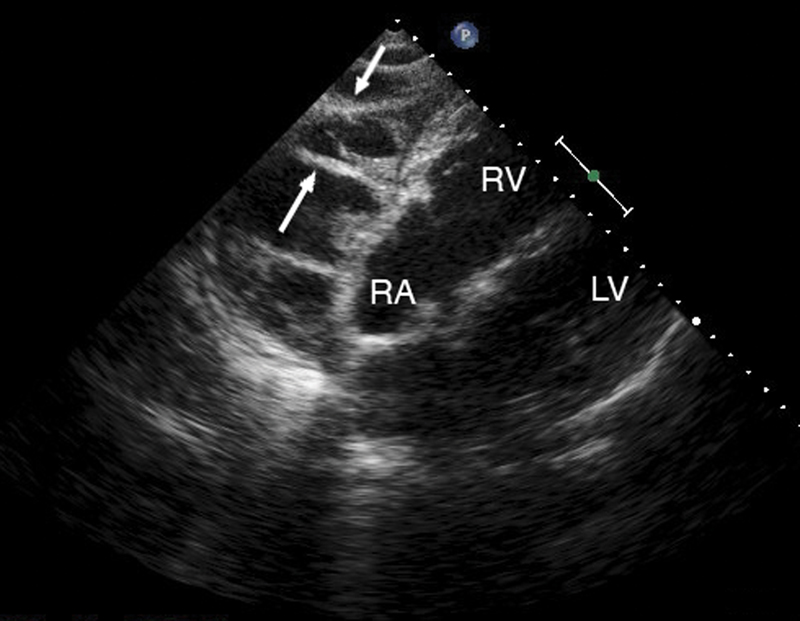

فحوصات تشخيصية لبعض امراض القلب والشرايين التاجية